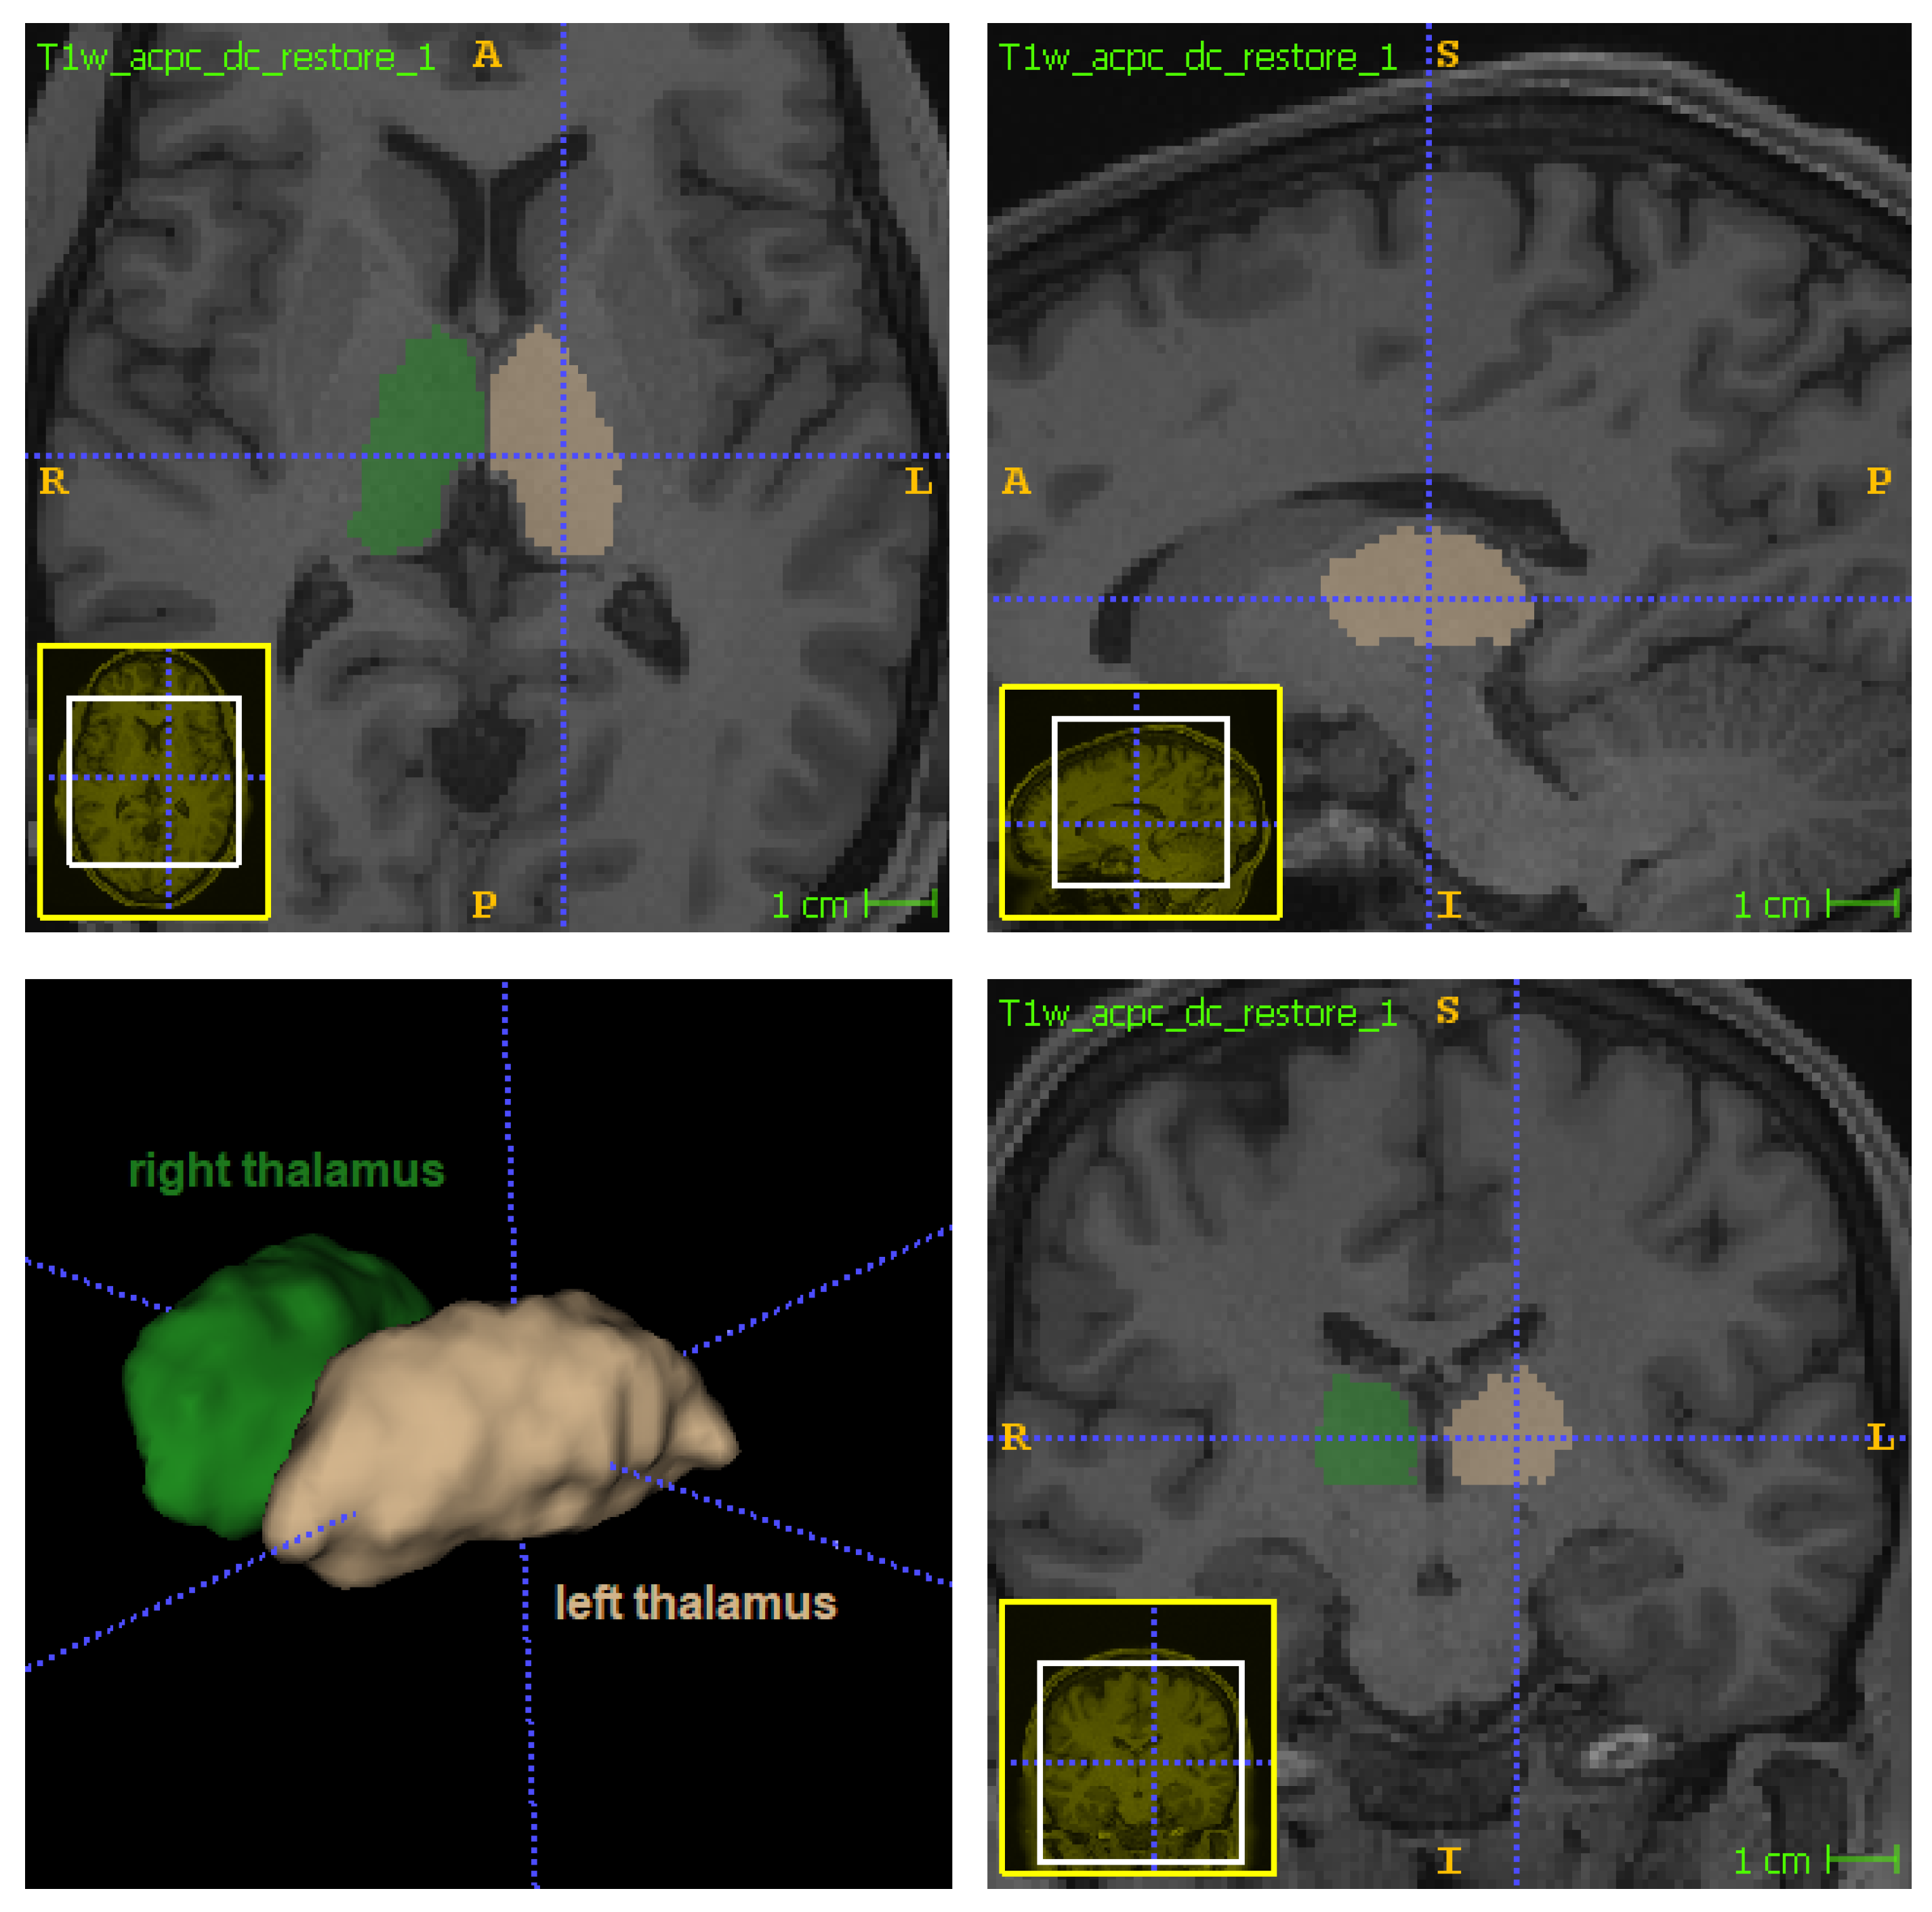

Figure 2.

Location of thalamus in orthogonal views: left thalamus in beige (label 10 in FreeSurferColorLUT) and right thalamus in green (label 49 in FreeSurferColorLUT).